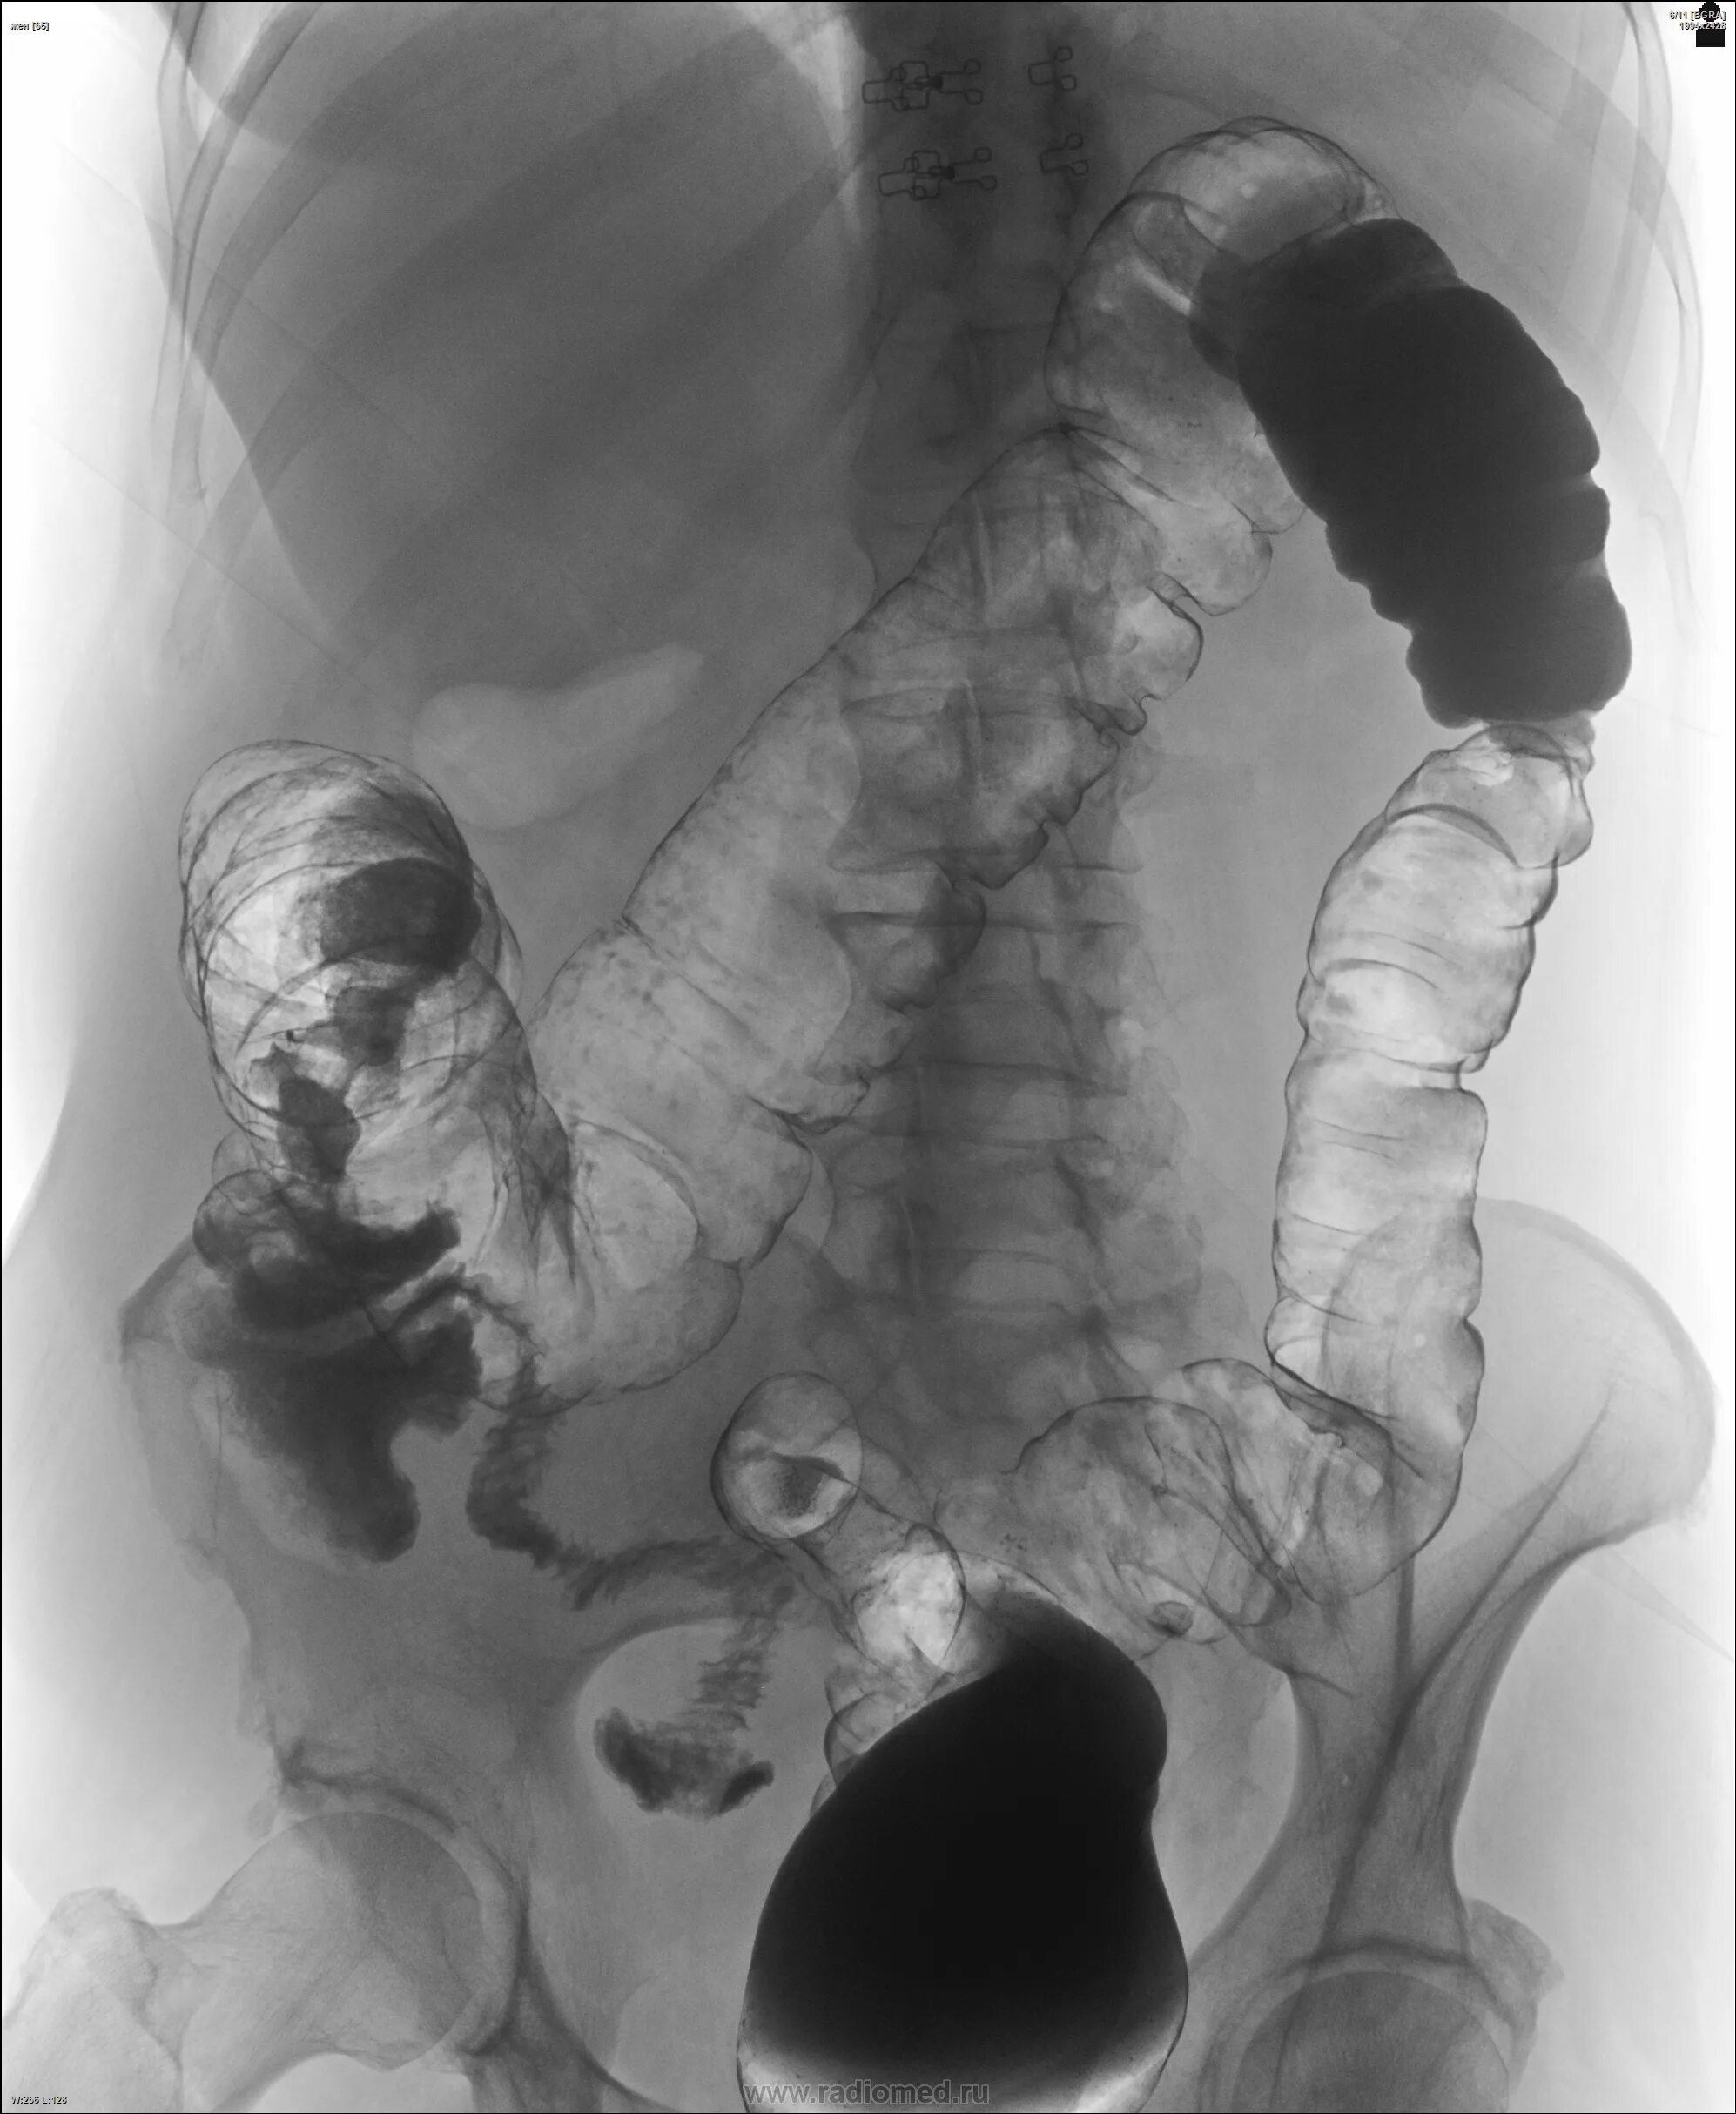

Ирригоскопия с двойным контрастированием